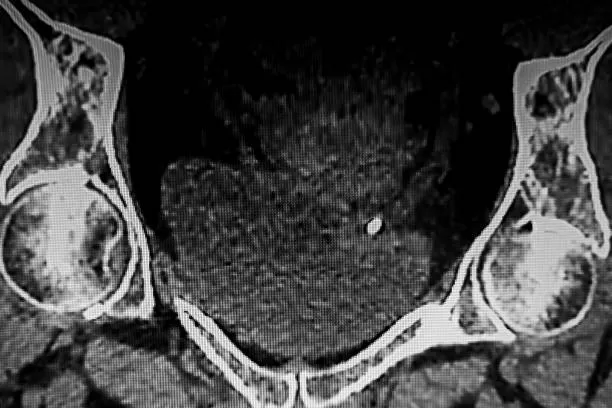

• Définition : la lithiase correspond à la formation de calculs pouvant varier en taille et en localisation, parfois asymptomatiques, parfois douloureux.

• Localisations possibles : elle peut toucher la vésicule biliaire, les reins ou encore les glandes salivaires, chaque localisation présentant ses spécificités.